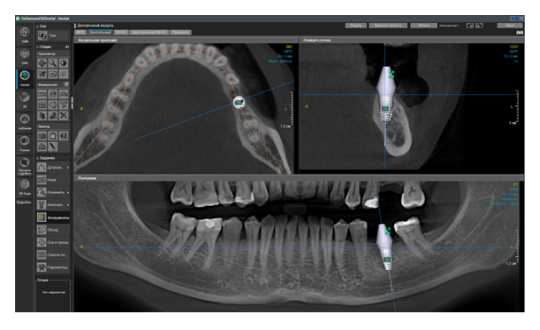

Когда мы отправляем пациента на проведение рентгенологического исследования, то подвергаем его определенному риску. Именно это нужно осознавать, так как в радиологии нет минимально безопасной дозы, поэтому любое назначение должно быть обоснованным. В связи с этим поле обзора является достаточно принципиальным параметром. Если вы врач-терапевт, занимающийся эндодонтией или ортопед, который решил оценить состояние зубов перед протезированием, то вы должны понимать, что проведение исследования с полем обзора 10x10 см будет гораздо информативнее нежели большие снимки (18x16 см и выше). В первую очередь это связано с размером вокселя, о нём я напишу чуть ниже, а второе это то, что вам придется увеличивать изображение по каждому корневому каналу, и от этого вы будете терять в качестве снимка (рис. 1). И ситуация наоборот, если вы ортодонт, то чтобы использовать весь диагностический потенциал, а также возможность загрузить данные для расчёта 3D цефалометрии, то вам нужны снимки, захватывающие весь лицевой отдел черепа. Таким образом, дентальный томограф должен обладать возможностью проведения исследований с разным FOV, обеспечивая нужды всех специалистов. Если ваша клиника базируется на терапевтическом, хирургическом и ортопедическом приёме, то на мой взгляд, можно рассмотреть дентальные томографы с полем обзора 10x10 см или 16x10 см. Последний больше актуален для тех, кто работает с ВНЧС, так как антропометрически в 16 см даже у брахицефалов сустав должен попадать. Если в клинике есть ортодонтическое направление, функциональная стоматология, ЛОР-практика или ЧЛХ, то, безусловно, вышепредставленные снимки не будут отражать всех данных, которые необходимы для диагностики и планирования лечения. Здесь лучше рассмотреть конусно-лучевые компьютерные томографы с зоной сканирования 18x16 или 20x20 см. Особо стоит отметить понятие «сшивки». Есть дентальные томографы, которые делают один цельный снимок размерами, которые описаны выше, а есть аппараты, которым нужно провести две экспозиции и сшить изображения вместе, чтобы получился необходимый объём исследования. Как правило, вторые томографы чуть дешевле, но всё зависит от того, насколько вам нужна максимальная точность исследования. Если при сшивке челюсти и зубы, как правило, совмещаются практически идеально, то на уровне позвоночного столба происходит наслоение тканей и от него уже не избавиться (рис. 2). Второй отрицательный момент – это износ оборудования, логично, что он будет быстрее, так что экономия средств — это ещё спорный вопрос.

Рис. 1. Представлены два исследования (10x10 см и 20x20 см). На обоих изображениях хорошо видна канально-корневая система зубов, но, если масштабировать второе исследование, то качество неминуемо снизится, как и диагностическая эндодонтическая эффективность.